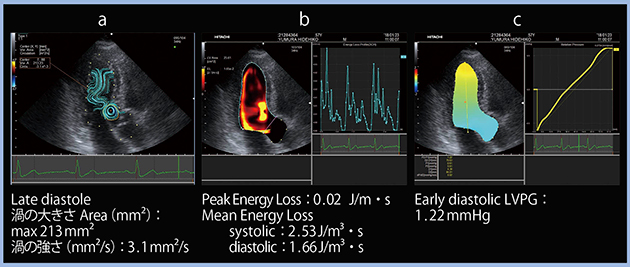

Case 1:50歳代,男性,健常例

本例は左房もそれほど大きくなく,左室の収縮力も十分保たれている。左室拡張能評価では,中隔側e’が8cm/s,E/e’が9,LAVIが28mL/m2,TR velocity(TRV)が2m/sと,ASE/EACVIガイドライン1)および日本循環器学会のガイドライン2)の基準値に照らして正常拡張と判断できる。また,左室・左房ストレインを計測したところ,GLSは−18.3%,LA strainは43%と正常範囲であった。

次に,VFMの流線表示のパラメータである渦について,特に拡張後期に絞って解析を行った。渦の大きさは最大213mm2,渦の強さは3.1mm2/sであった(図1 a)。エネルギー損失は,Peak Energy Lossが0.02J/m・s,Mean Energy Lossは収縮期が2.53J/m3・s,拡張期が1.66 J/m3・sと低かった(図1b)。LVPGは,early diastolic LVPGが1.22mmHgであった(図1 c)。なお,VFMの各種パラメータは正常値が定義されておらず,上記はあくまでも健常例の一例における数値であることをご理解いただきたい。

図1 健常例におけるVFMのパラメータ

a:流線表示(渦の評価) b:エネルギー損失 c:LVPG